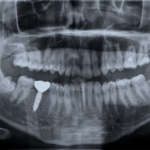

La terapia non chirurgica della perimplantite risulta efficace nell’arrestare la perdita ossea progressiva, ridurre il sondaggio e la suppurazione e raggiungere il bone fill radiografico nella maggior parte dei casi.

Indicazione del consensus meeting FDI 2018 su perimplantite e terapia non chirurgica

In caso di perimplantite può essere necessario aggiungere nel piano di cure anche una terapia di tipo chirurgico. Al contrario, nel caso in cui il trattamento di prima linea risulti sufficiente a riportare sotto controllo i parametri parodontali, può essere necessario impostare un mantenimento a cadenza al massimo semestrale.

Tessuti perimplatari e perimplantite

La perimplantite è una condizione patologica che porta a progressiva perdita del sostegno osseo di un impianto già precedentemente osteointegrato, che può pertanto andare incontro a fallimento secondario